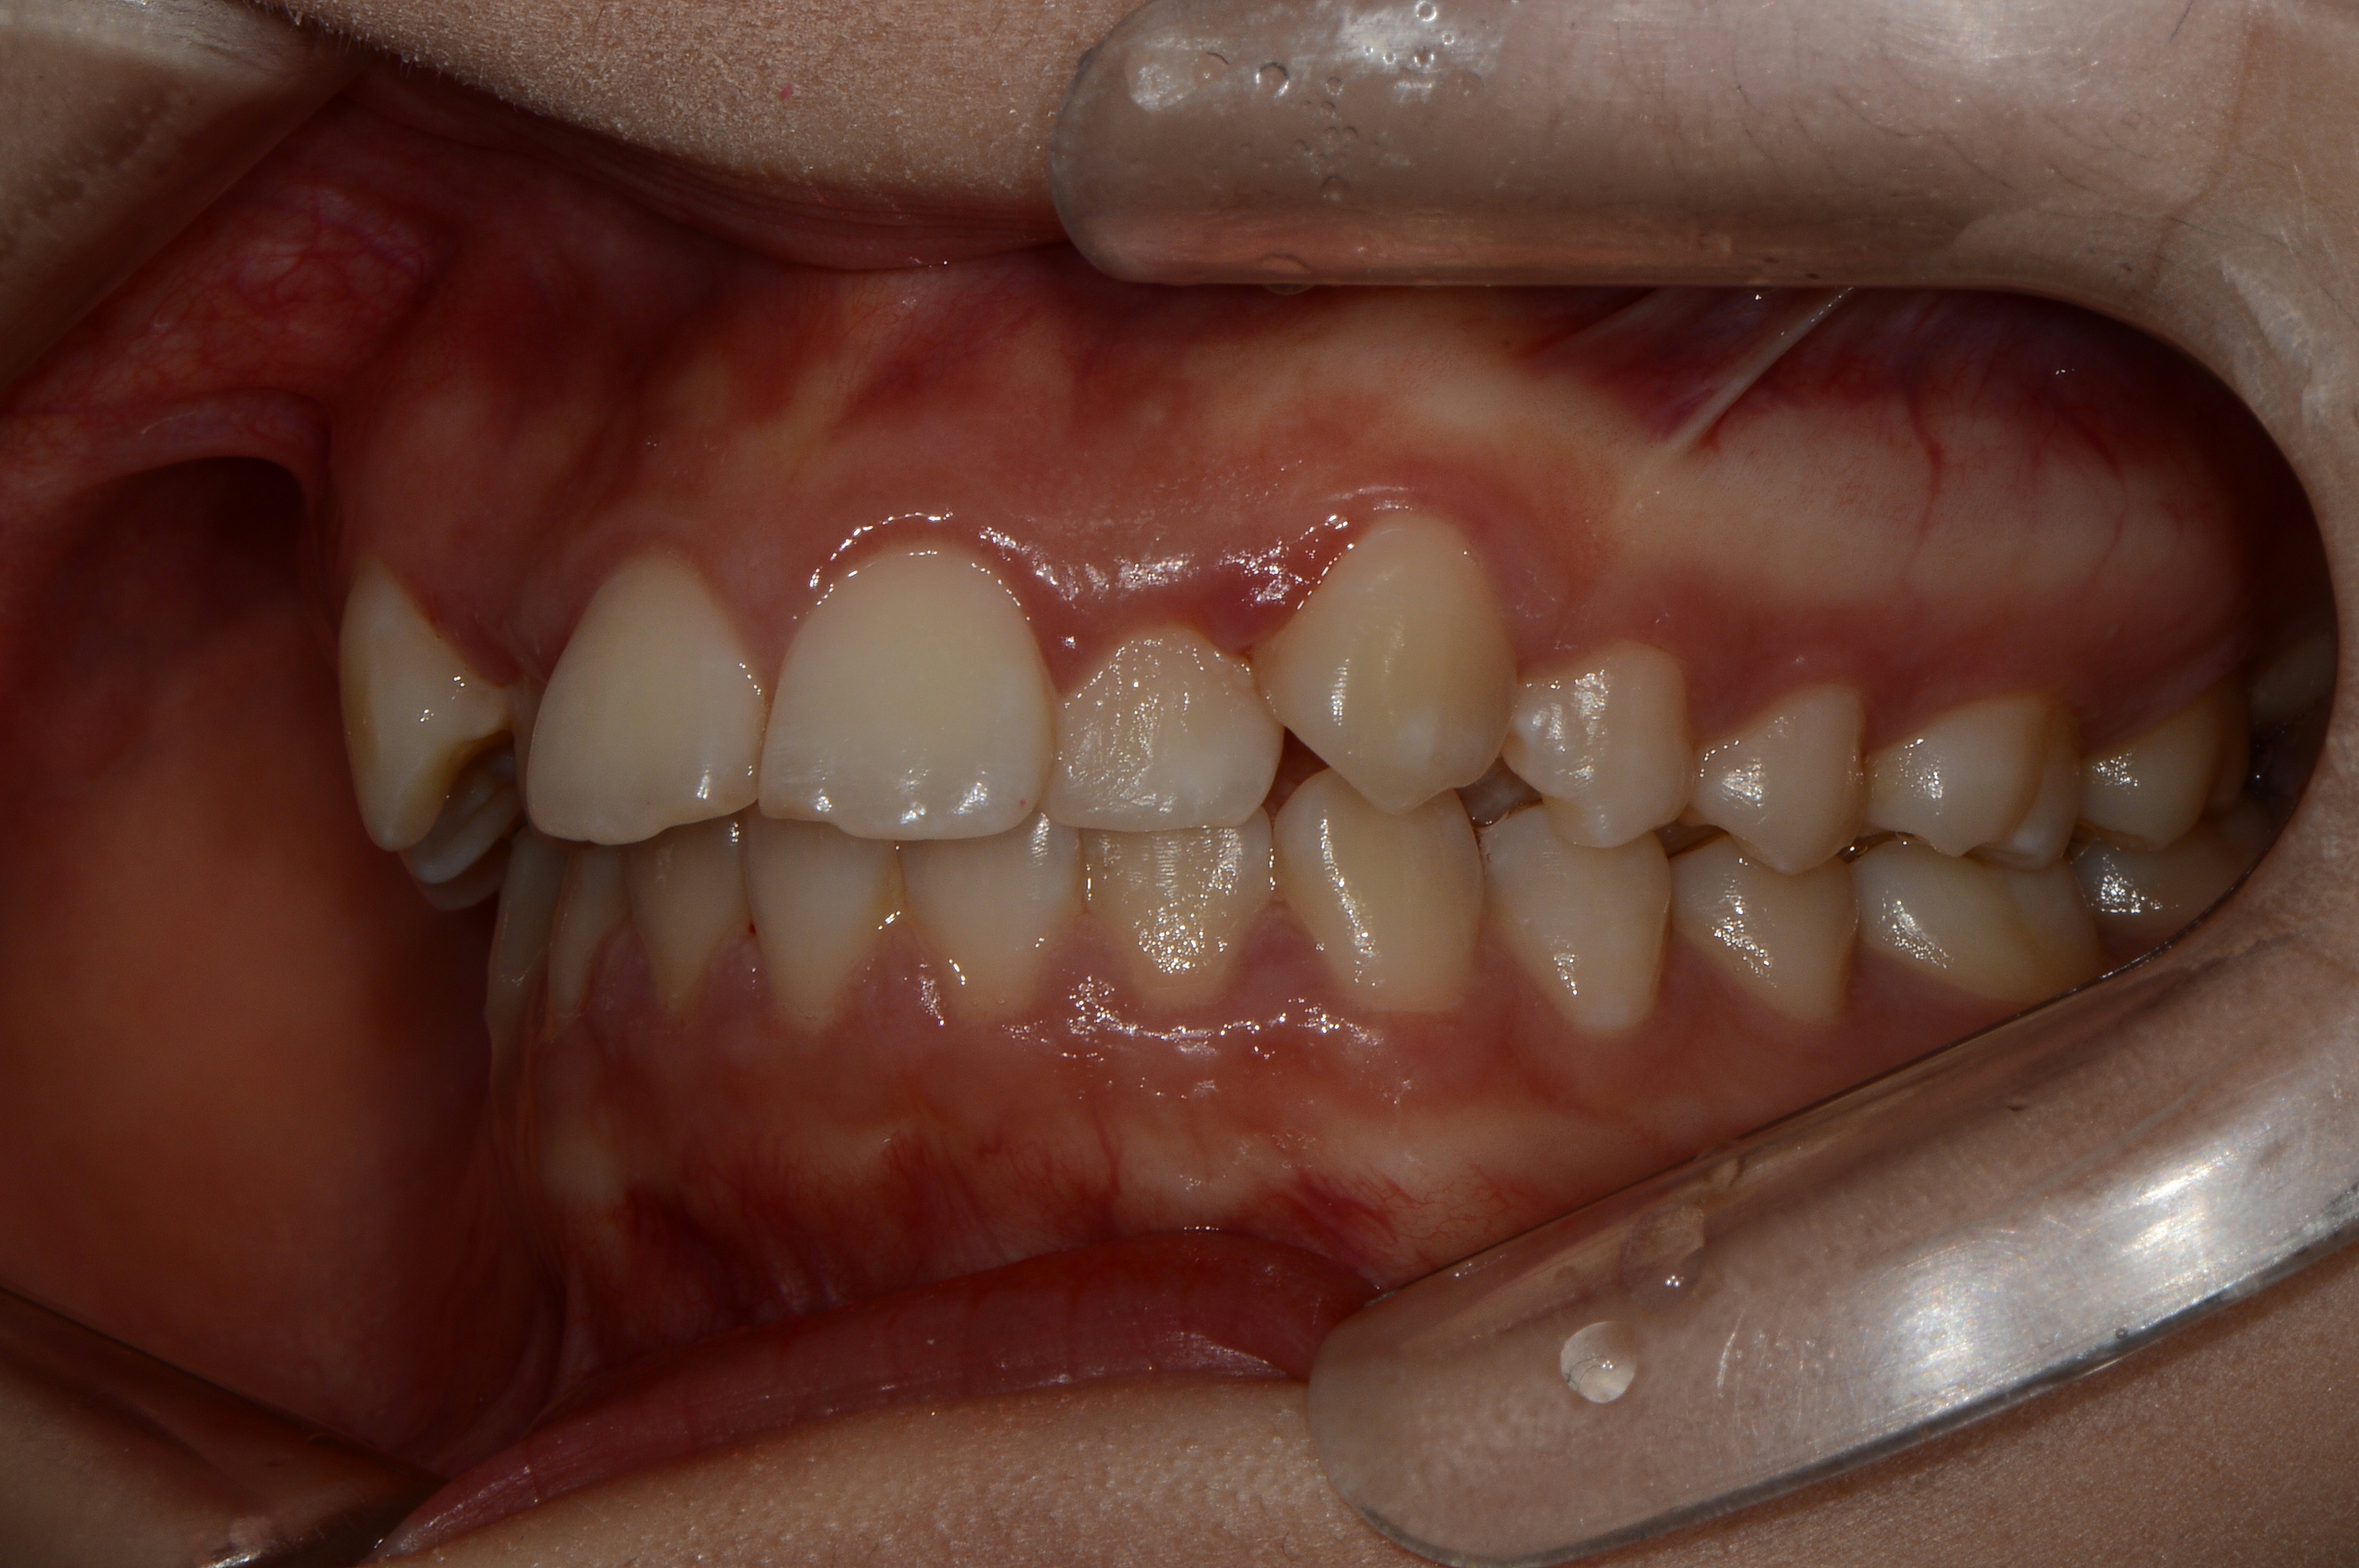

치료 전 사진입니다.